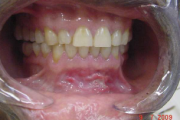

Mehaaniline trauma

pidev põse närimine